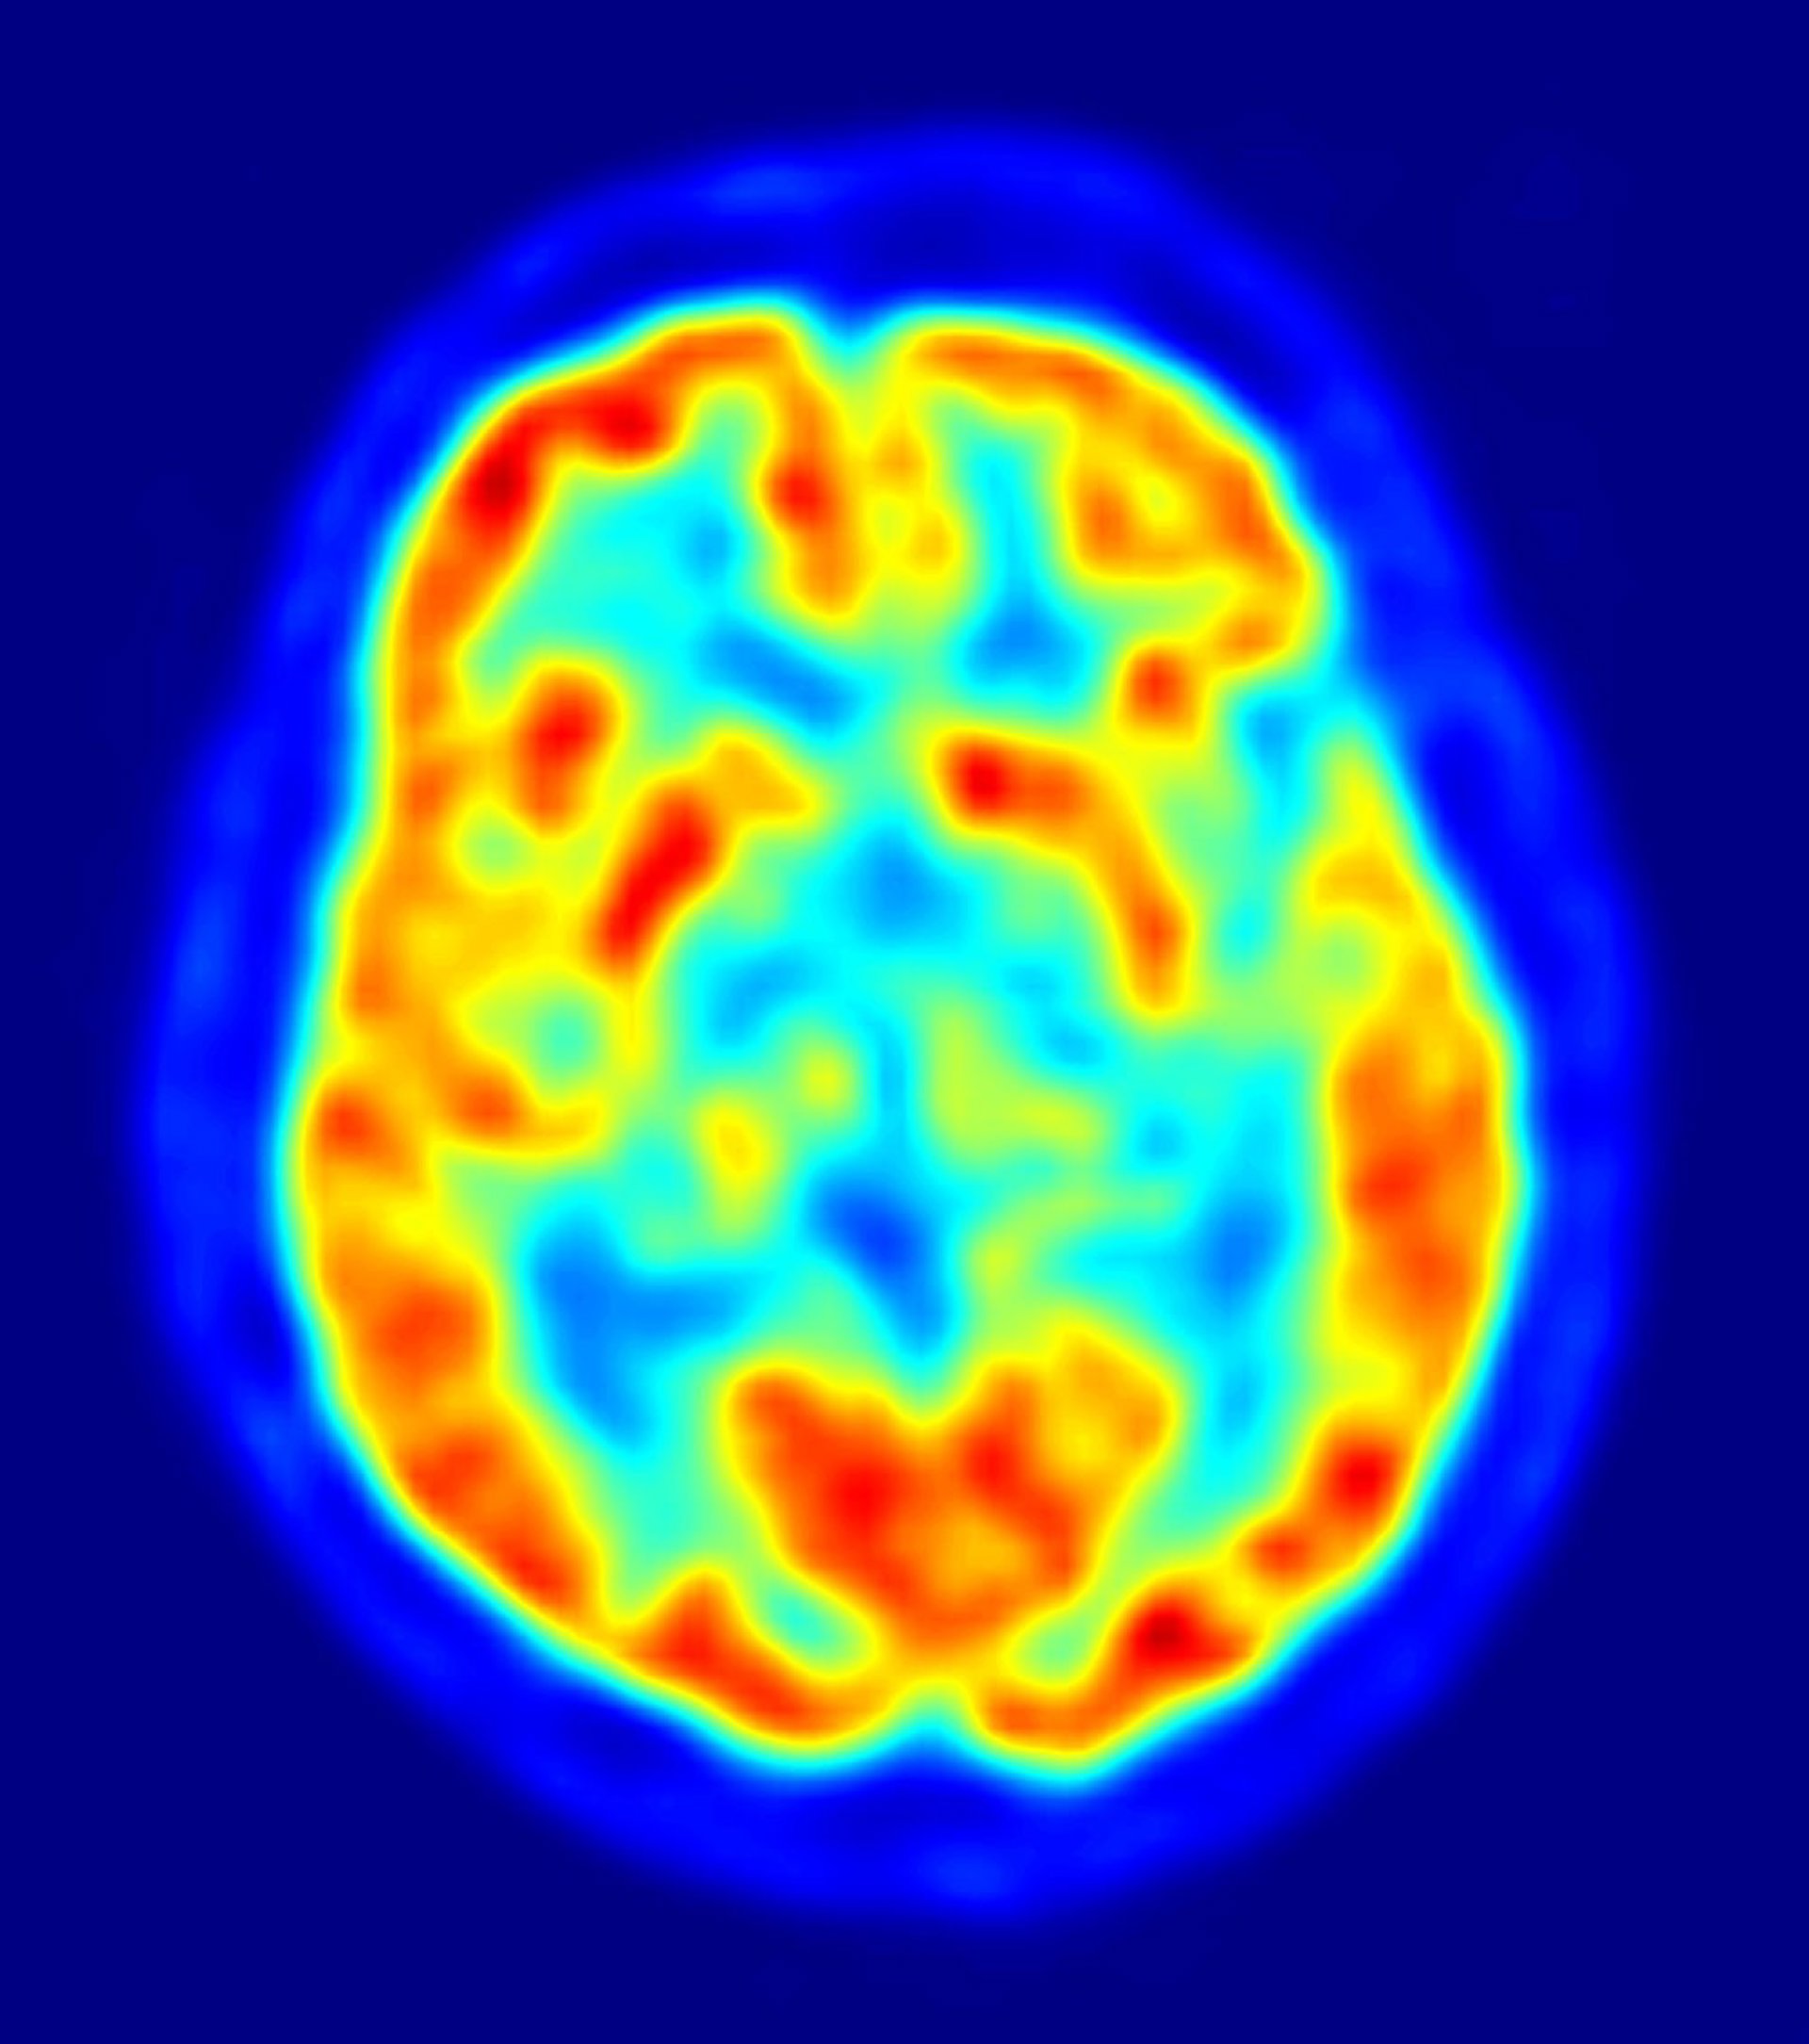

La reparación en el nivel celular del hipotálamo - una región crítica y compleja del cerebro que regula fenómenos como el hambre, el metabolismo, la temperatura corporal y comportamientos básicos, como el sexo y la agresión - indica la posibilidad de nuevos enfoques terapéuticos para condiciones de mayor nivel como la lesión de médula espinal, el autismo, la epilepsia, la esclerosis lateral amiotrófica (enfermedad de Lou Gehrig), la enfermedad de Parkinson y la enfermedad de Huntington.

"Sólo hay dos áreas del cerebro conocidas que se someten normalmente al reemplazo neuronal durante la edad adulta a nivel celular - la llamada neurogénesis, o nacimiento de nuevas neuronas - el bulbo olfativo y una subregión del hipocampo llamada circunvolución dentada", explica Jeffrey Macklis, profesor de Biología Regenerativa en Harvard, quien añade que "las neuronas que se añaden durante la edad adulta en ambas regiones son generalmente pequeñas, y se cree que actúan como los controles de volumen de la señalización específica. En nuestro nuevo estudio hemos reconectado circuitos cerebrales dañados que no experimentan naturalmente la neurogénesis, y hemos conseguido restaurar su función normal".

Para trasplantar las células exactamente en la región correcta y microscópica del hipotálamo, los científicos utilizaron una técnica llamada microscopía de alta resolución por ultrasonidos. Las neuronas sobrevivieron al proceso de trasplante y se desarrollaron estructural, molecular y electrofisiológicamente; además estas nuevas neuronas se integraron funcionalmente en los circuitos, respondiendo a insulina, la leptina, y la glucosa.